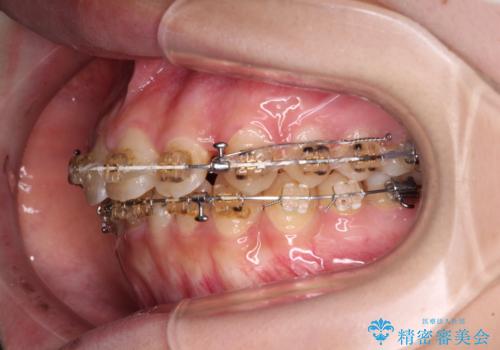

- 矯正装置

- 審美装置

- 大学病院にて装置を装着したものの、治療が十分に受けることができないとのことで転院をされた患者様です。

上顎歯列が前方にあり、口元が閉じにくくなっていたため、既に装着されている装置を使用して上顎歯列全体を後方に移動させていくこととしました。

舌の突出癖があり、それが原因で上下前歯に隙間ができていたため、改善のためのトレーニングを行うように指示をしました。